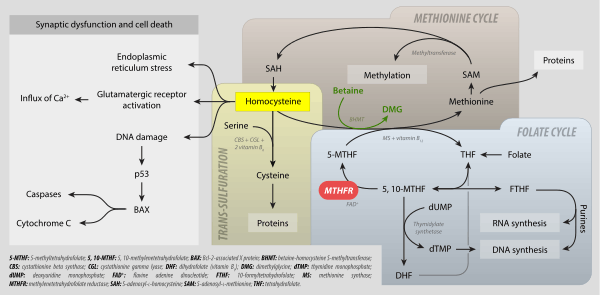

Levomefolic acid (INN) (also known as L-5-MTHF, L-methylfolate and L-5-methyltetrahydrofolate and (6S)-5-methyltetrahydrofolate, and (6S)-5-MTHF) is the primary biologically active form of folate used at the cellular level for DNA reproduction, the cysteine cycle and the regulation of homocysteine. It is also the form found in circulation and transported across membranes into tissues and across the blood-brain barrier. In the cell, L-methylfolate is used in the methylation of homocysteine to form methionine and tetrahydrofolate (THF). THF is the immediate acceptor of one carbon units for the synthesis of thymidine-DNA, purines (RNA and DNA) and methionine. The un-methylated form, folic acid (vitamin B9), is a synthetic form of folate, and must undergo enzymatic reduction by methylenetetrahydrofolate reductase (MTHFR) to become biologically active.[1]

It is synthesized in the absorptive cells of the small intestine from polyglutamylated dietary folate. It is a methylated derivative of tetrahydrofolate. Levomefolic acid is generated by MTHFR from 5,10-methylenetetrahydrofolate (MTHF) and used to recycle homocysteine back to methionine by methionine synthase (MS).[2]